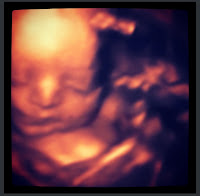

WE TREATED OURSELVES TO ANOTHER 3D SESSION FOR MOTHER'S DAY. WE ACTUALLY WENT ON MOTHER'S DAY BEFORE WE WENT TO BRUNCH WITH OUR HANDSOME SONS, BUT LIL MISS WAS UNCOOPERATIVE SO WE WERE RESCHEDULED FOR THIS PAST FRIDAY. HERE ARE SOME PICS OF OUR 3 BEAUTIFUL KIDS.

| THIS IS MY FAVORITE ONE |